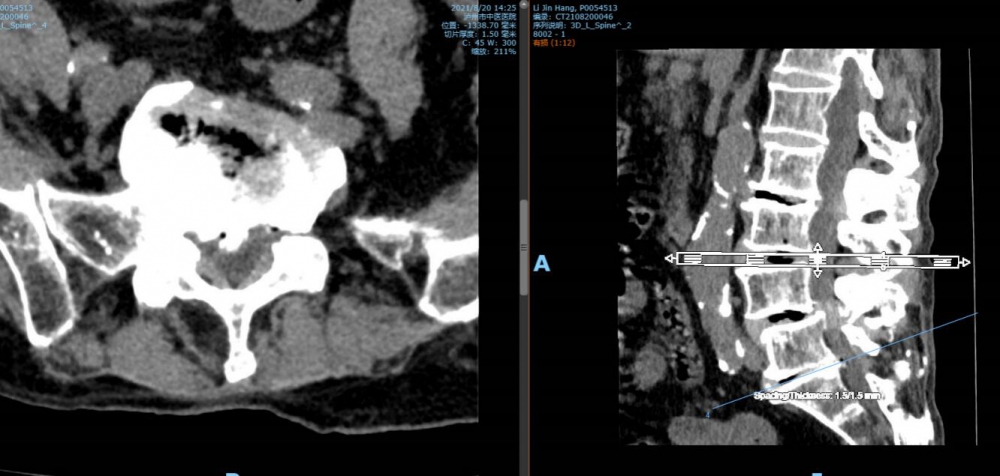

腰5 骶1椎間盤CT

腰5 骶1椎間盤MRI